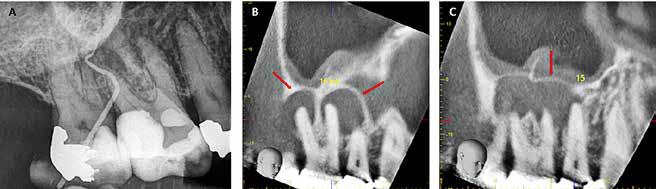

A. Klinisk foto af lateral incisiv i overkæben med lyserød plet svarende til kronens cervikale del. B. Røntgenoptagelse viser resorption i tandens koronale del. C. CBCT viser velafgrænset rodresorption på kronens labiale overflade (pil). D. Invasiv cervikal rodresorption på første molar i underkæben (pil). E. Ekstern rodresorption på 5- og den mesiale rod på 6- (pil).

Fig. 14. Root resorption. A. Clinical photo showing a maxillary lateral incisor with a pink spot on the cervical part of the crown. B. Radiograph showing resorption in coronal part of the tooth. C. CBCT image showing a well circumscribed root resorption on labial surface (arrow) of the crown. D. Cervical invasive root resorption on mandibular right first molar (arrow). E. External root resorption on mandibular right second premolar and mesial root of first molar (arrow).

Rodresorption er tab af hårde tandvæv (dentin og cement) som følge af osteoklastisk aktivitet. Skaderne er irreversible, og prognosen er usikker selv efter en kombination af forskellige behandlingstiltag. Rodresorptioner inddeles i interne og eksterne efter læsionens beliggenhed. Anvendelse af CBCT har gjort det lettere at diagnosticere og behandle rodresorptioner (Fig. 14A-C). Selvom de fleste eksterne rodresorptioner kun inddrager en enkelt tand, er der dog patienter, som rammes af multiple rodresorptioner (Fig. 14D og E). Da rodresorptioner er så svære at behandle, placeres de i Kategori D.